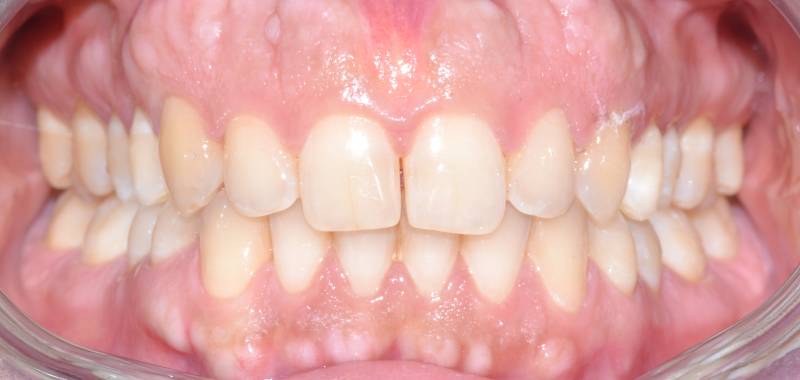

Paziente trattato con ortodonzia tradizionale fissa bimascellare per 20 mesi.